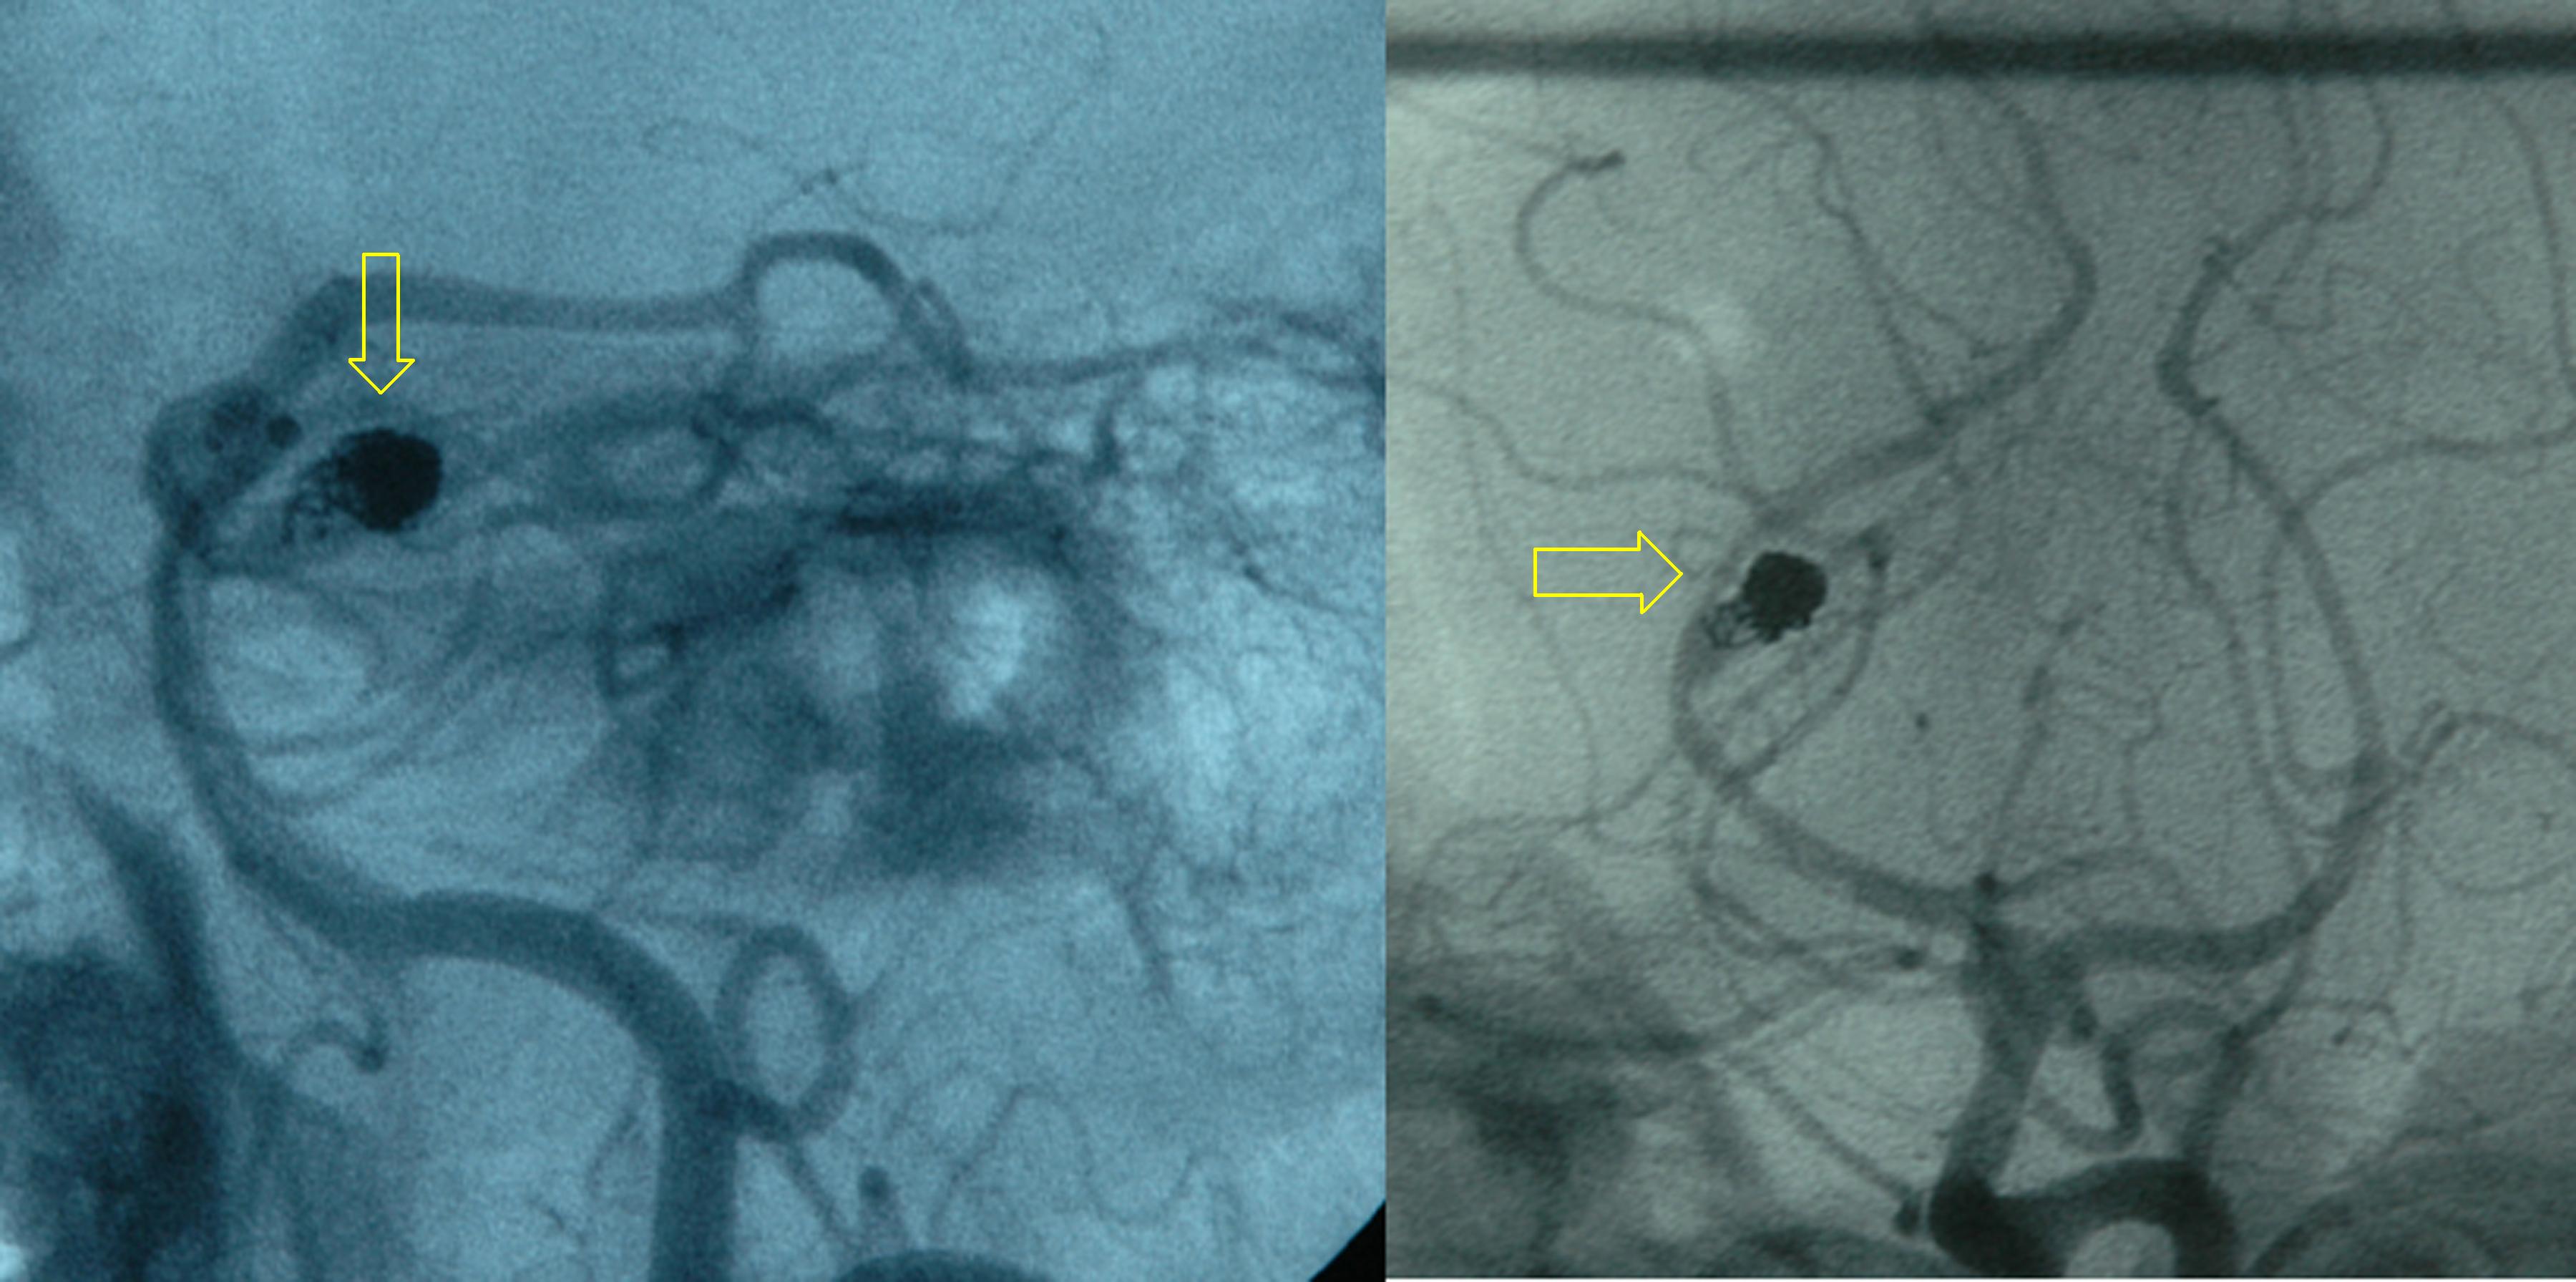

뇌혈관조영술은 뇌동맥류나 뇌동정맥 기형 등 출혈 원인을 확인하는 데 사용된다.[3] 혈관을 촬영하는 방법으로는, X선 검사를 하면서 카테터로 조영제를 주입하여 촬영하는 경동맥 조영술과 추골 동맥 조영술이 가장 민감도와 특이도가 높다.

뇌동맥류 파열 시 재출혈 예방을 위해 개두술을 이용한 클립 결찰술 또는 혈관 내 코일 색전술을 시행한다.[54][55] 클립 결찰술은 개두술로 동맥류를 찾아 목 부분에 클립을 끼운다.[54] 코일 색전술은 사타구니 대퇴 동맥에 카테터를 삽입, 백금 코일을 동맥류에 넣어 혈전을 만들고 폐쇄한다.[55] 치료법은 환자 상태, 동맥류 위치 및 크기를 고려해 신경외과 의사, 신경 방사선과 의사 등 다학제 팀이 결정한다.[3]중대뇌동맥 및 관련 혈관 동맥류는 혈관조영술 접근이 어려워 클리핑이 적합하고, 기저 동맥과 후대뇌동맥 동맥류는 수술 접근이 어려워 혈관 내 코일 색전술이 용이하다.[56]